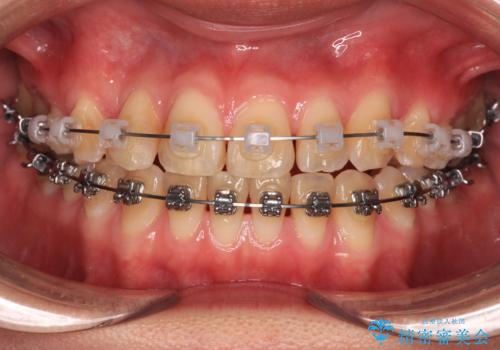

上下前歯のデコボコを気にして来院された患者様です。

ワイヤー矯正でもマウスピース矯正でも可能でしたが、短期間で、自身の手を煩わせることなく治療を行いたいとのことで、ワイヤー装置にて矯正治療を行うこととしました。

舌の突出癖により、治療過程でスペースが多くできましたが、舌のトレーニングを頑張っていただき、1年強で終えることができました。